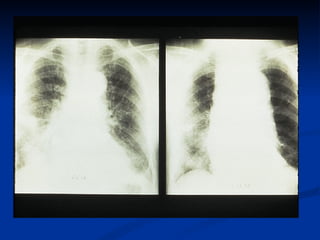

CHEST X-RAY 1. widened mediastinum, (sen: 44-80%) 2. Calcium sign -Displaced intimal calcification (>10mm) from outer aortic wall– useful in older patients 3.pleural effusion (involvement of descending aorta) 4.Normal in 18% A Normal CXR Should Not Deter Further Evaluatio n.

CHEST X-RAY 1.widened mediastinum, (sen: 44-80%) 2. Calcium sign -Displaced intimal calcification (>10mm) from outer aortic wall– useful in older patients 3.pleural effusion (involvement of descending aorta) 4.Normal in 18% A Normal CXR Should Not Deter Further Evaluatio n.